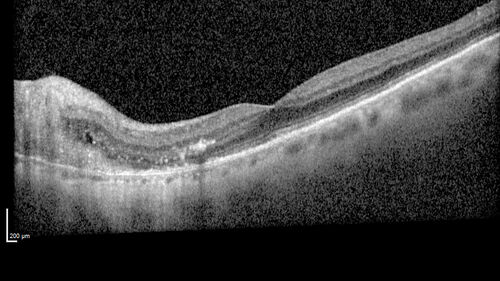

Peripapillary CNVM No Treatment

85 year old with peripapillary CNVM watched for many years.